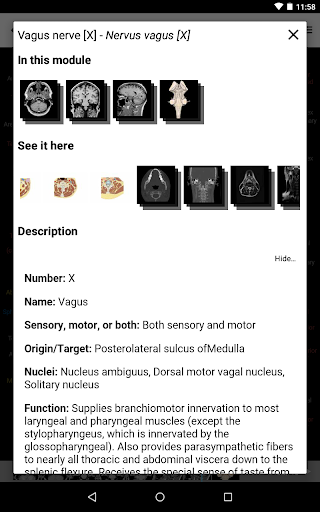

e-Anatomy tiene más de 26 000 imágenes que contienen series de imágenes en vistas axiales, coronales y sagitales, así como radiografías, angiografías, imágenes de disección, gráficos anatómicos e ilustraciones. Todas las imágenes médicas fueron etiquetadas cuidadosamente, más de 967 000 etiquetas disponibles en 12 idiomas, incluida la Terminologia Anatomica latina.

- Toque las etiquetas para mostrar las estructuras anatómicas